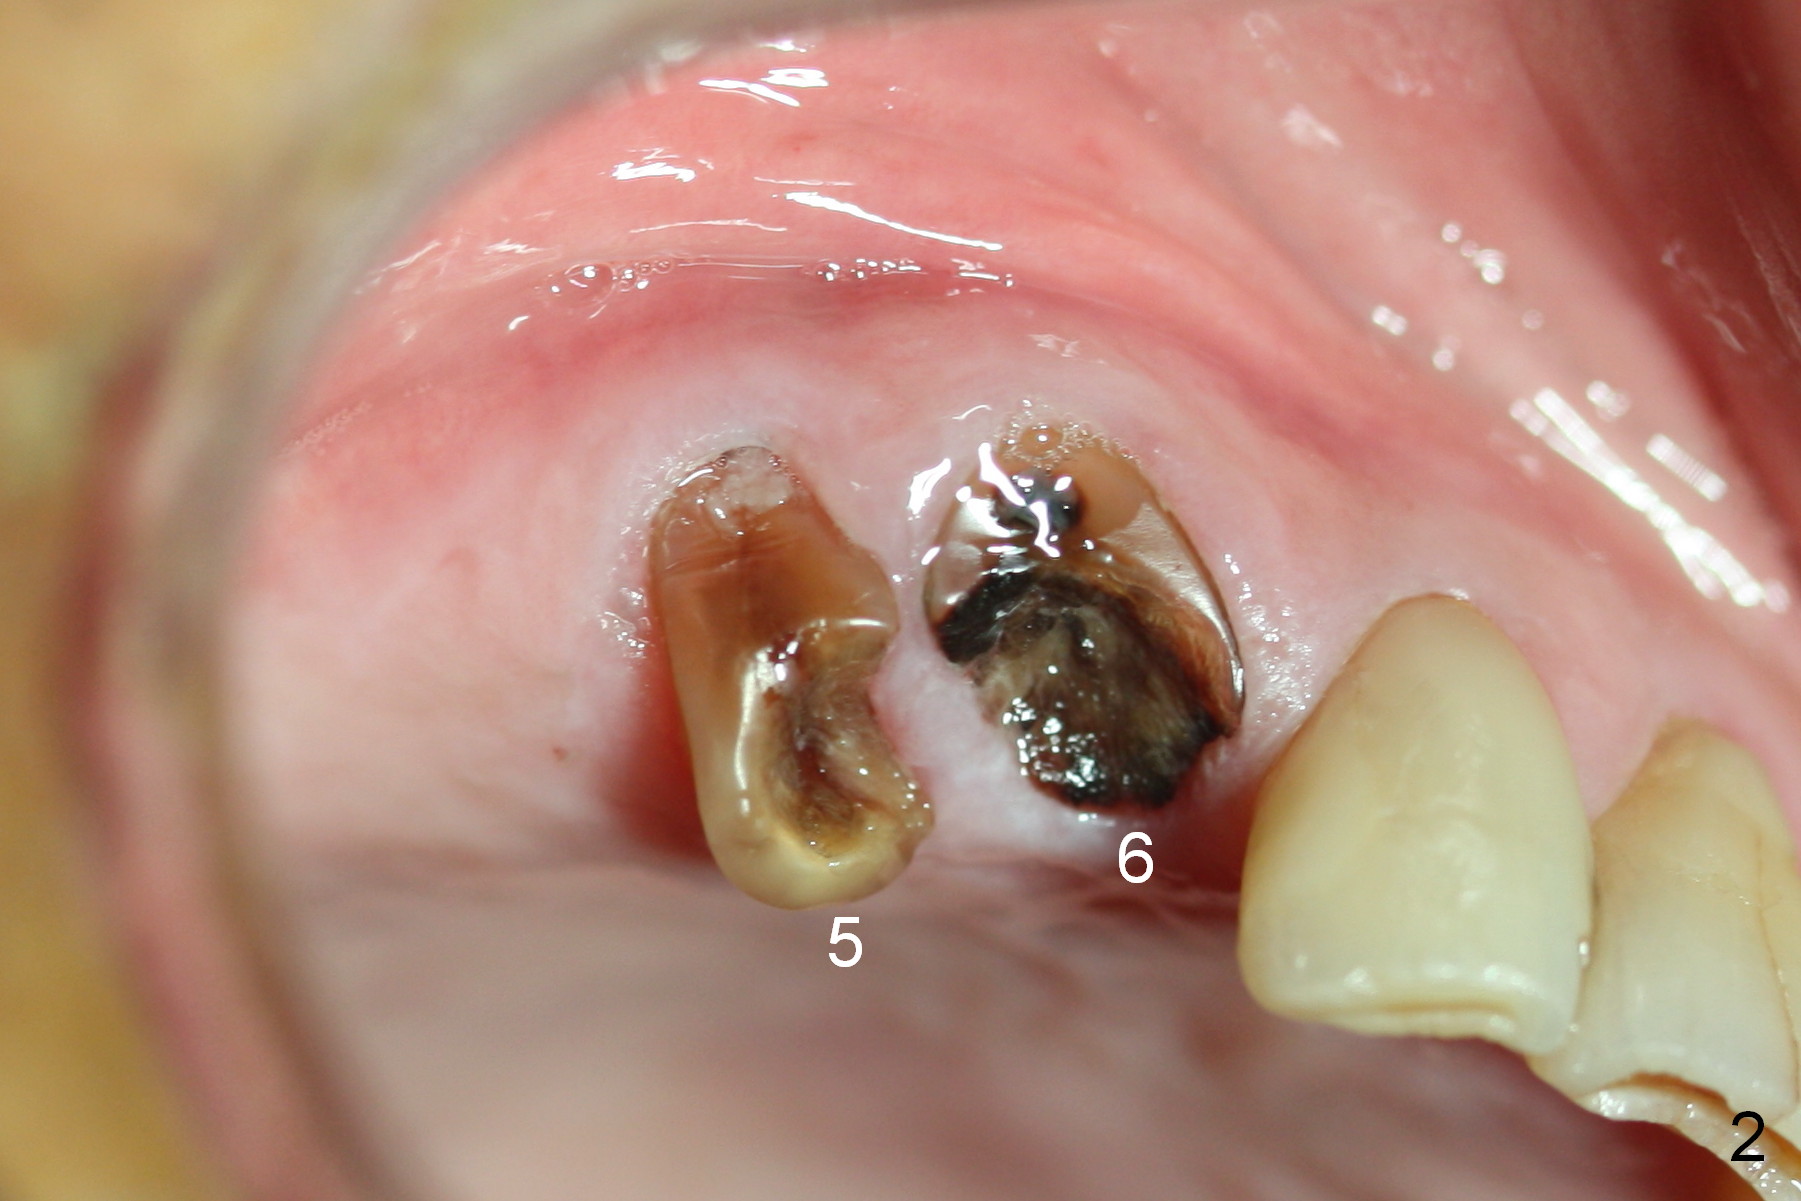

Several of CK's upper teeth (apparently in cross bite) are to be restored with implants (Fig.1).  The first two are #5 and 6; note the oval roots (Fig.2).  After extraction, and curettage, osteotomy starts in the palatal aspect of each socket.  The 1st intraop PA shows that the trajectory at #6 is incorrect (Fig.3).  After adjustment, osteotomies look parallel (Fig.4: D: 3.5x20 mm drill; T: 4.5x20 mm tap).  This suggests how important it is to use parallel pins to check initial osteotomies for neighboring implants (Fig.3).  The trajectory of the implants remains acceptable (Fig.5: 4.5x20 mm with insertion torque »60 Ncm); so is the position of the implants (as palatal as possible; Fig.6 (*: bone graft)).   Immediate provisionals are fabricated in cross bite.